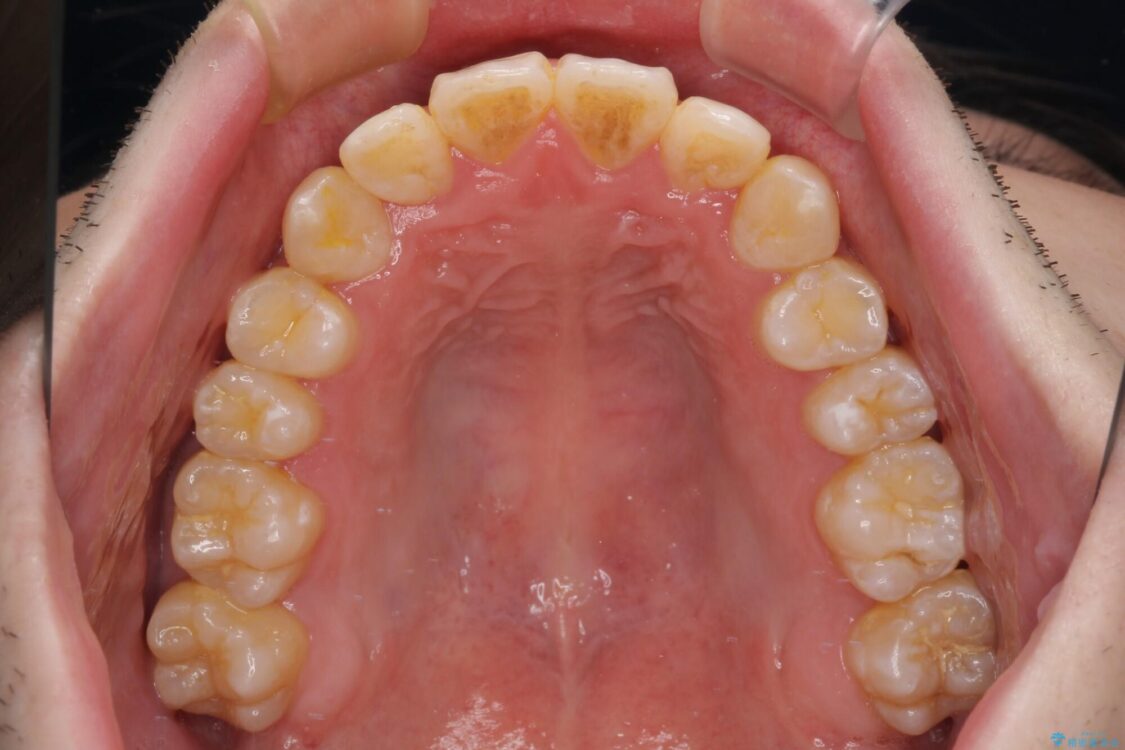

治療後

シザーズバイトは強く咬合する奥歯を移動させるため、多くの場合においてワイヤー矯正の装置のみでは改善が困難となります。

奥歯の咬み合わせ改善は治療初期からしっかりとアプローチする必要があるため、補助装置を積極的に利用します。